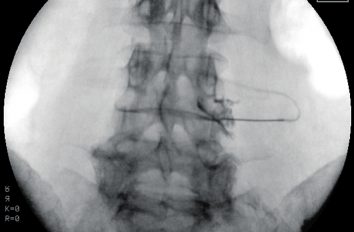

Interventionelle Schmerztherapie

Dr. med.Tim Reck, MSc

Interventionelle schmerztherapeutische Verfahren spielen heute sowohl in der Behandlung akuter wie zunehmend auch chronischer Schmerzen eine wichtige Rolle.